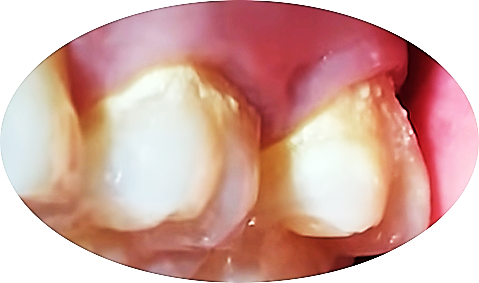

치석은 침이 많이 나오는 침샘 부근에 있는 치아에 주로 많이 생깁니다.

혀밑 침샘이 있는 아랫니 안쪽

그리고 귀밑 침샘이 있는 윗니 어금니 바깥쪽에 많이 생깁니다.